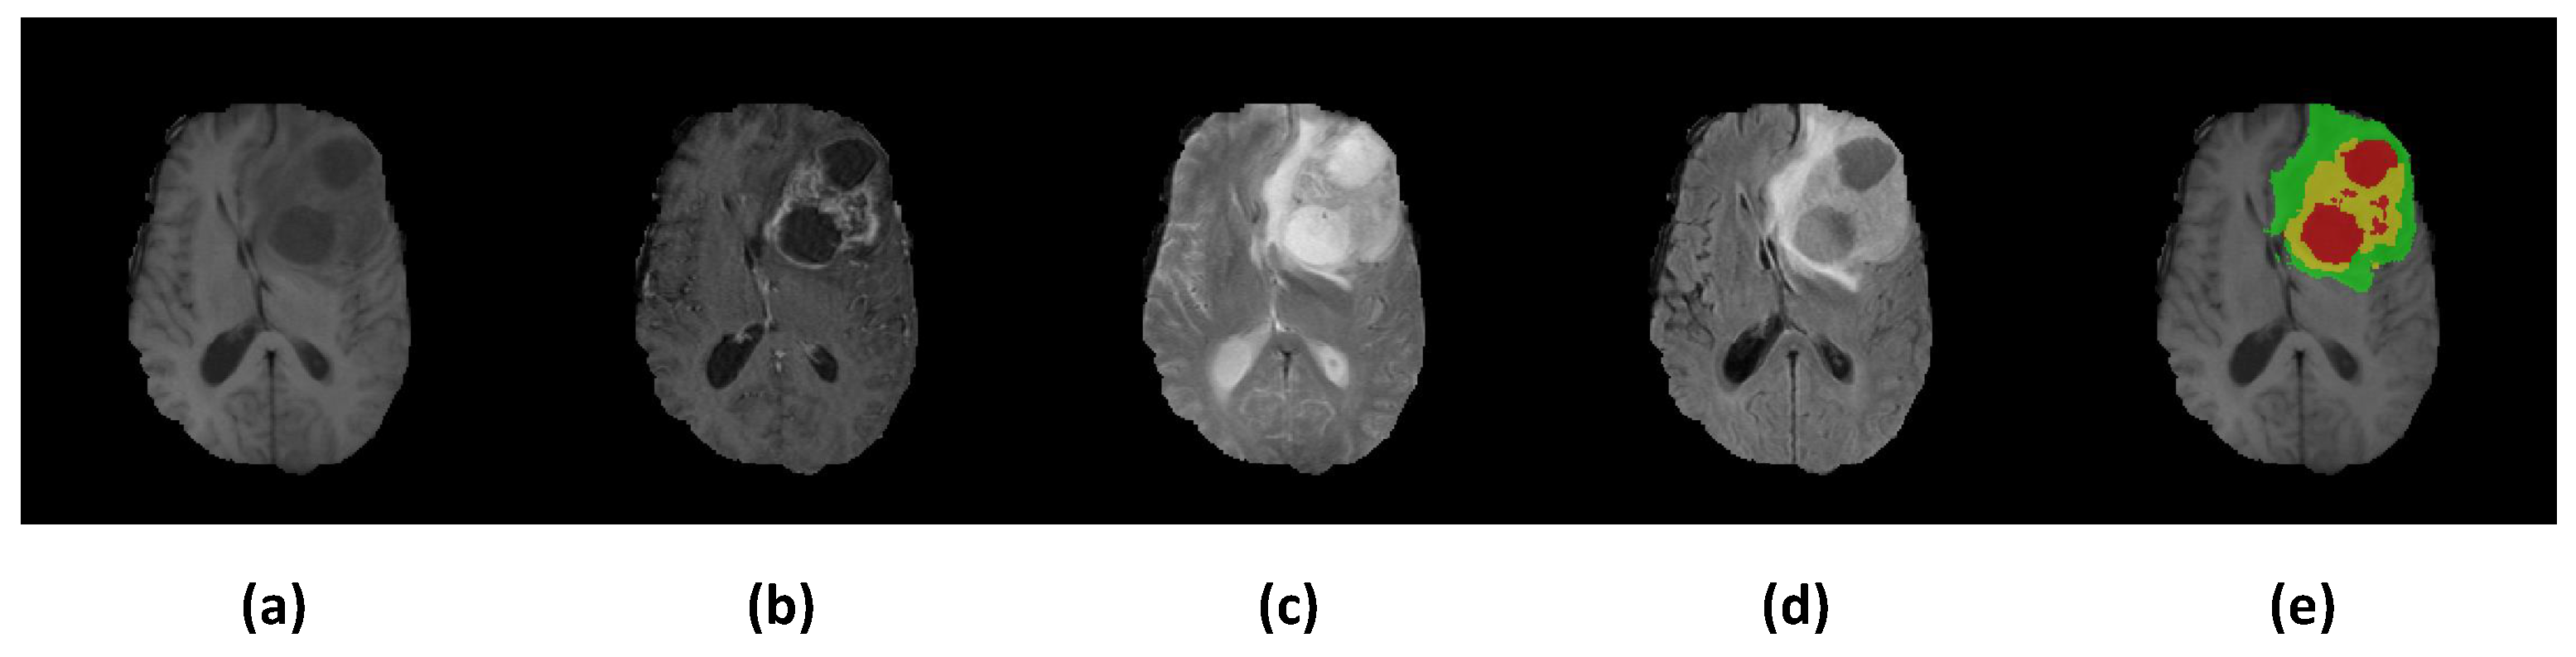

3.1. Dataset